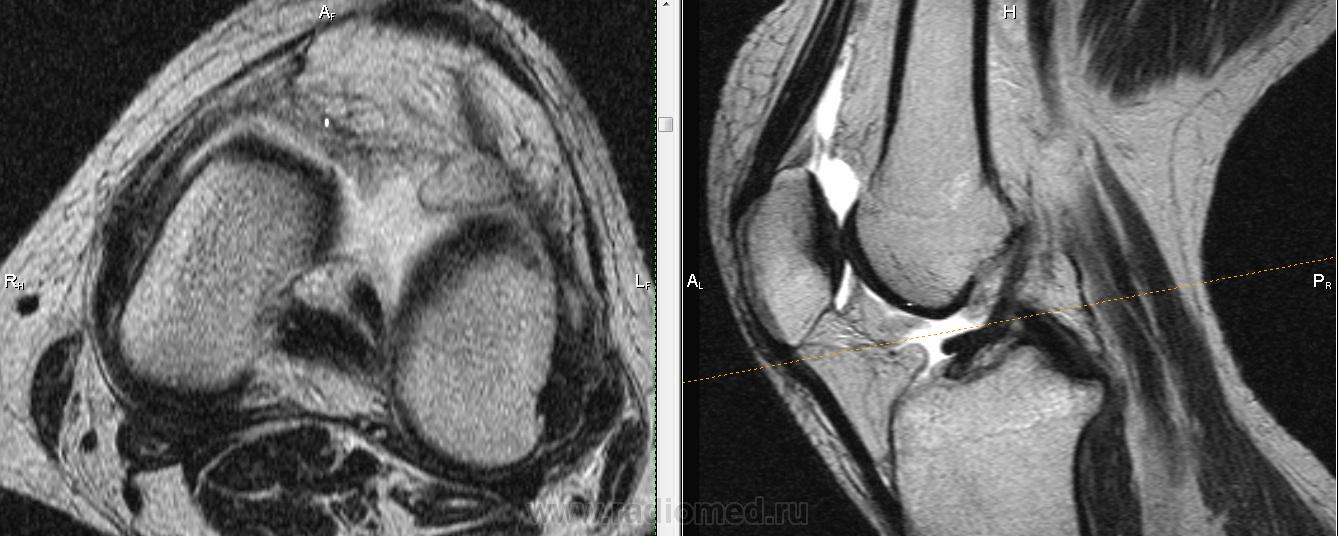

Падение с велосипеда. Вперед выступает фрагмент ПКС?

Не очень понятно, Михаил Александрович.Как-будто бы симптом "двойной  крестообразной связки", но не совсем похоже: при  этом  связка как-бы дугообразно идет.И мениски визуально вроде бы целы.Не может это быть фрагментом  переднего рога мениска?

Трудно сказать, на фрагмен мениска более похоже. Да и ПКС не отечная и внутренний мениск какой-то дефицитный. Если вопрос о цесостности ПКС обычно косая проекция выручает.

Думаю , тут фрагмент   переднего рога и части тела  латерального мениска ,  он(фрагмент) совсем  оторвался и уплыл кпереди .